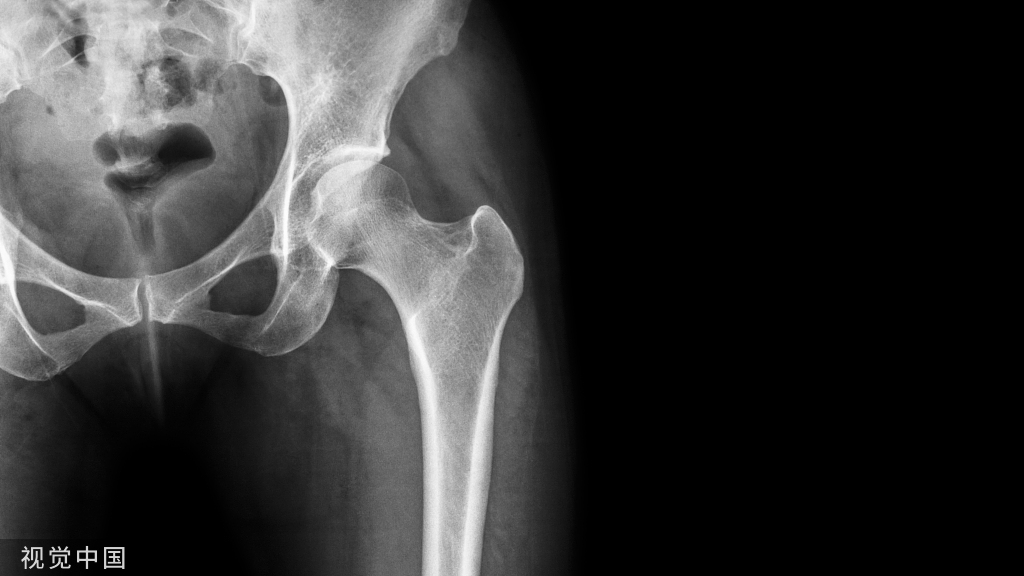

手术后留在体内的钢板,到底取不取?

你是否也有过这样的疑问,骨科术后常会在体内留下钢板,那么它到底要不要取出来?

其实,骨科手术中置入的钢板属于“内固定物”的一种,同样在手术中广泛应用的还应髓内钉、克氏针、螺钉等。